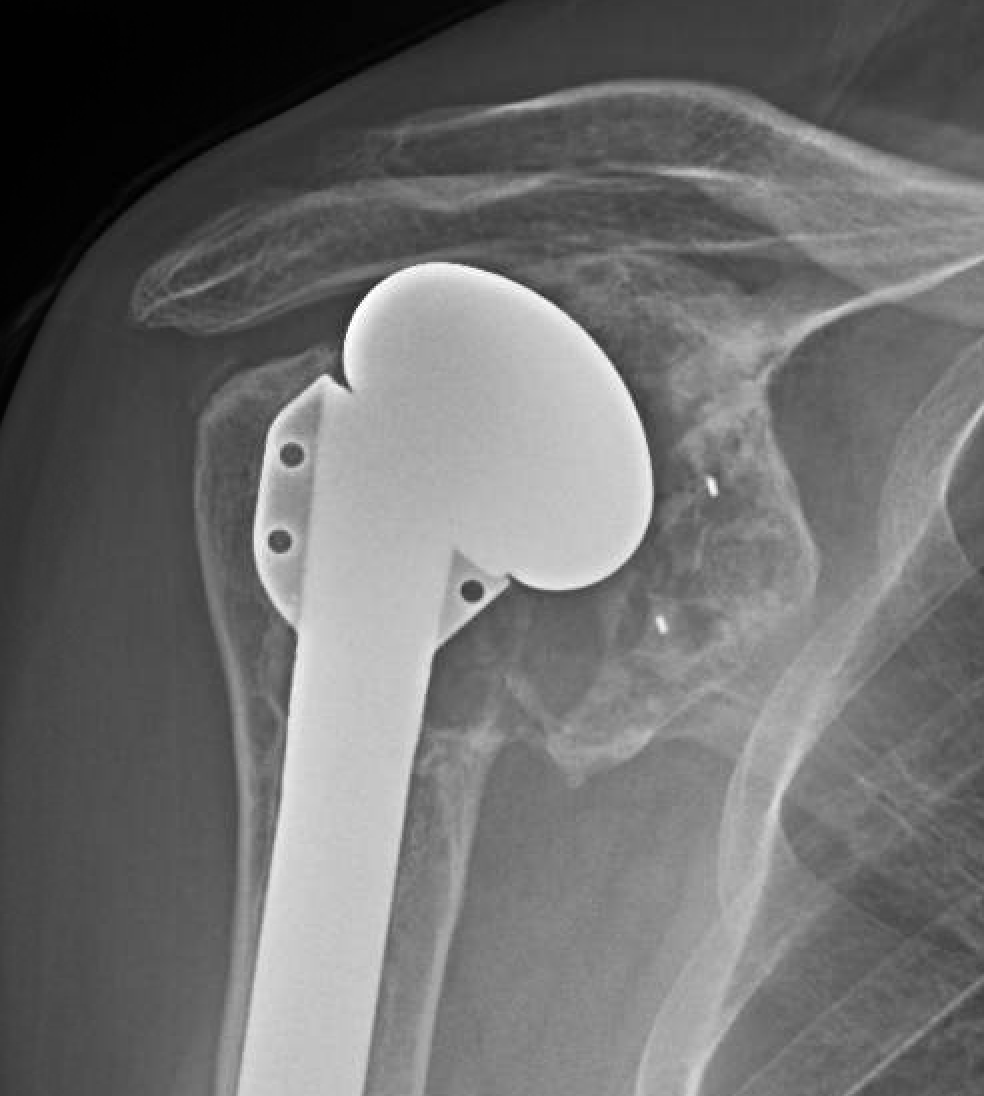

An active outdoorsman presented with a painful shoulder and a history of three prior right shoulder surgeries, the most recent being a total shoulder. His x-rays showed a superiorly placed humeral component and massive glenoid osteolysis.

A year later, he went on to have his arthritic left shoulder managed with a ream and run